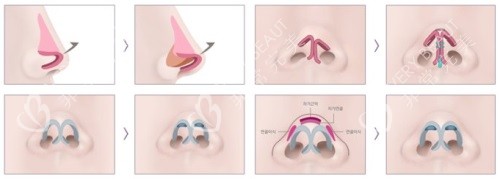

李保锴的鼻修复技术特点

他擅长采用肋软骨、鼻中隔等自体材料进行鼻部重建,重视鼻部功能与形态协调。尤其在处理鼻小柱疤痕、鼻翼后缩、鼻孔不对称等复杂问题时经验充足。

李医生强调鼻部设计的整体协调,推崇自然风格的鼻型。术后结果不仅触感柔软,还可揉捏,且长期稳定性较好,力求减少再次修复的可能。

从公开病例来看,李保锴医生曾处理过多例高难度修复手术,包括四次鼻修复史及注射物取出的情况。术后结果在形态和对称度上均有良好表现,受到较多患者认可。